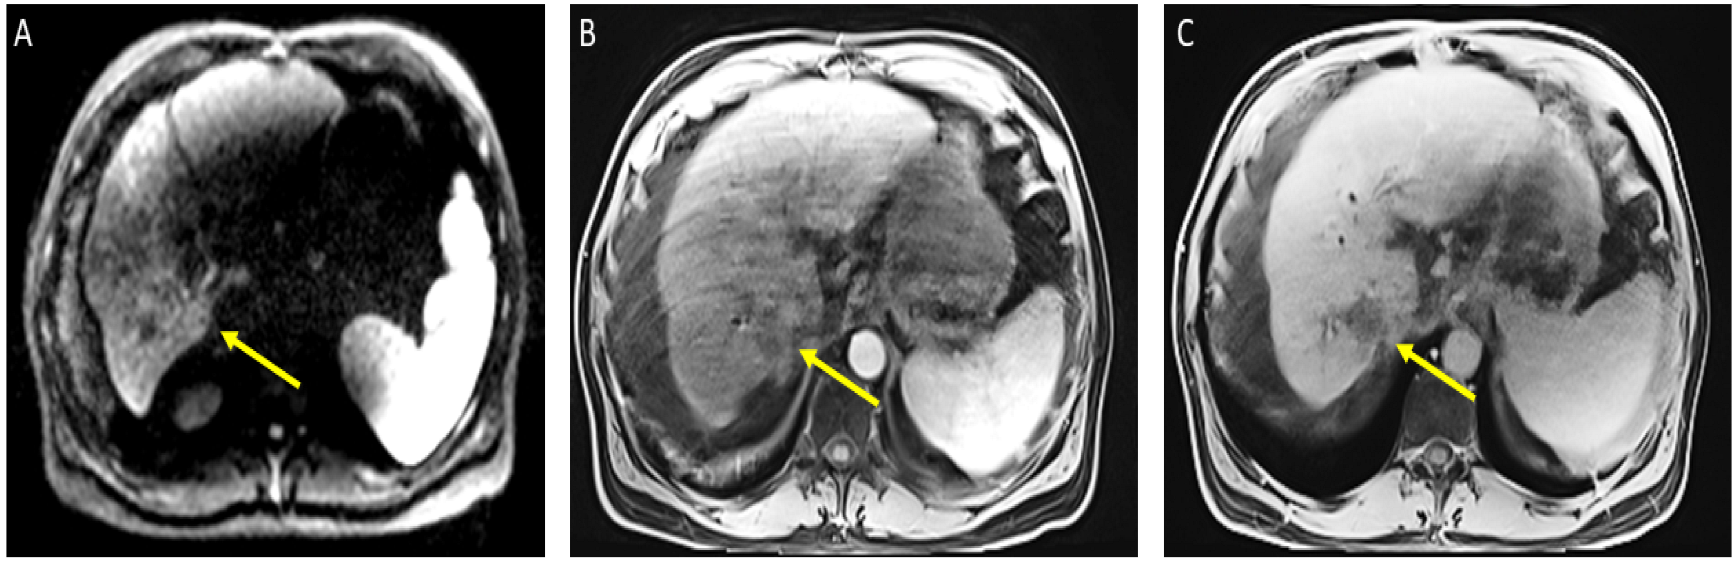

From a radiological perspective, the imaging plays a role in HCC diagnosis by detecting lesions, stratifying them based on standardized imaging features (LI-RADS), and providing staging information. Imaging also guides treatment by evaluating response to therapy or identifying the spread of disease; our patient had no postoperative complications or graft rejection. At his around 1-year post-transplant follow-up the patient continues to be in good health with a stable graft and no signs of cancer recurrence (Figure 4).

Figure 4.

Magnetic resonance imaging of the abdomen. T1 with contrast, orthotopic liver transplant has been successfully achieved, no mass, and the impression is normal (captured at the post-transplant follow-up visit).